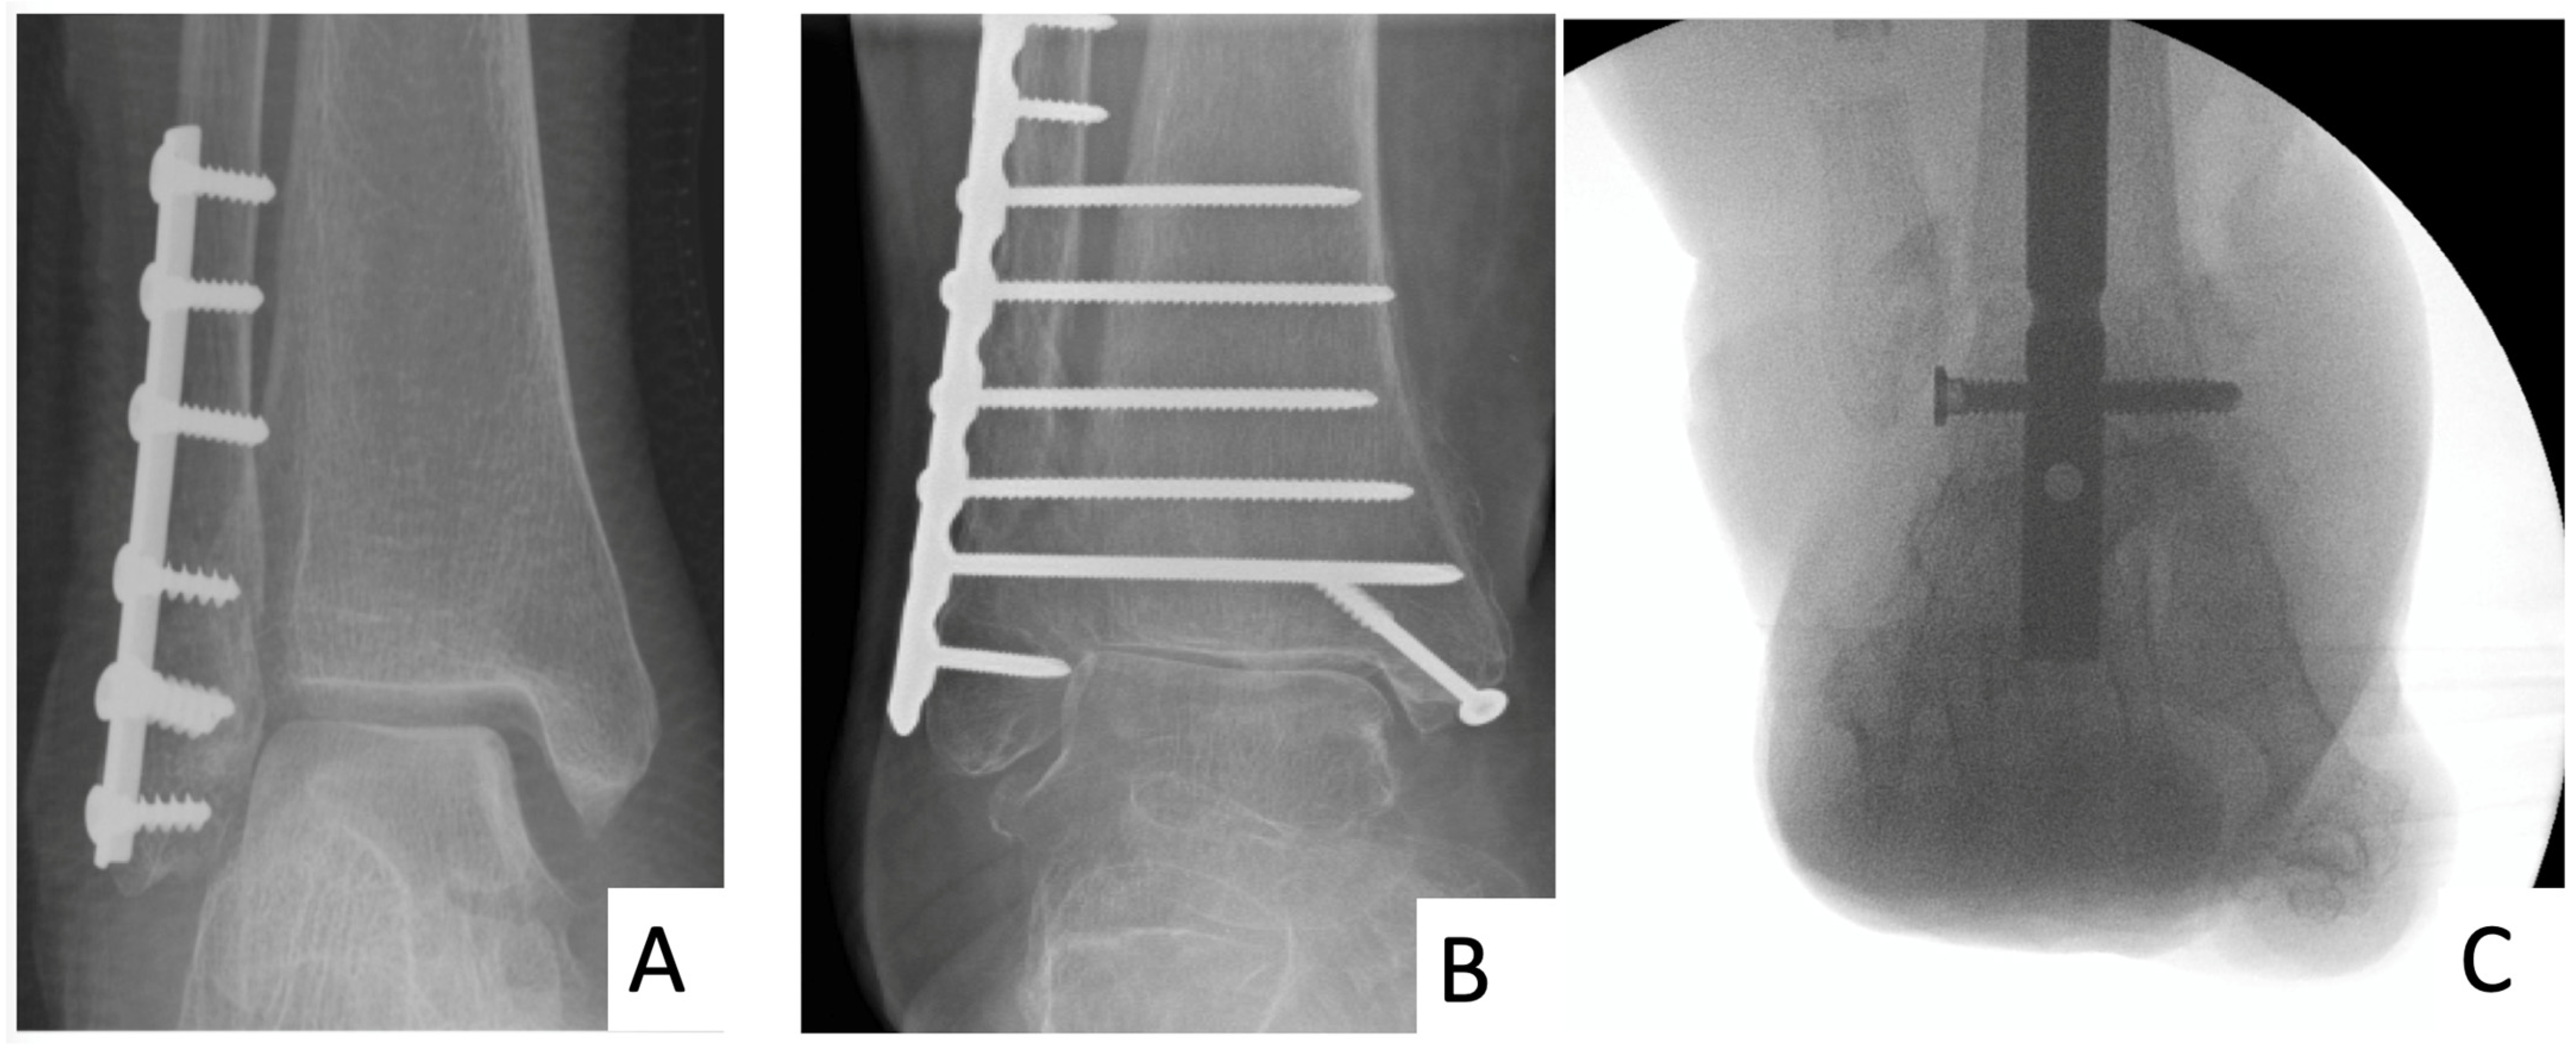

3.2. HFN

4.4. Challenging Surgical Dogma: The Potential of HFN and Extended ORIF in Limiting Post-Operative Immobilisation/Non-Weightbearing in Diabetes